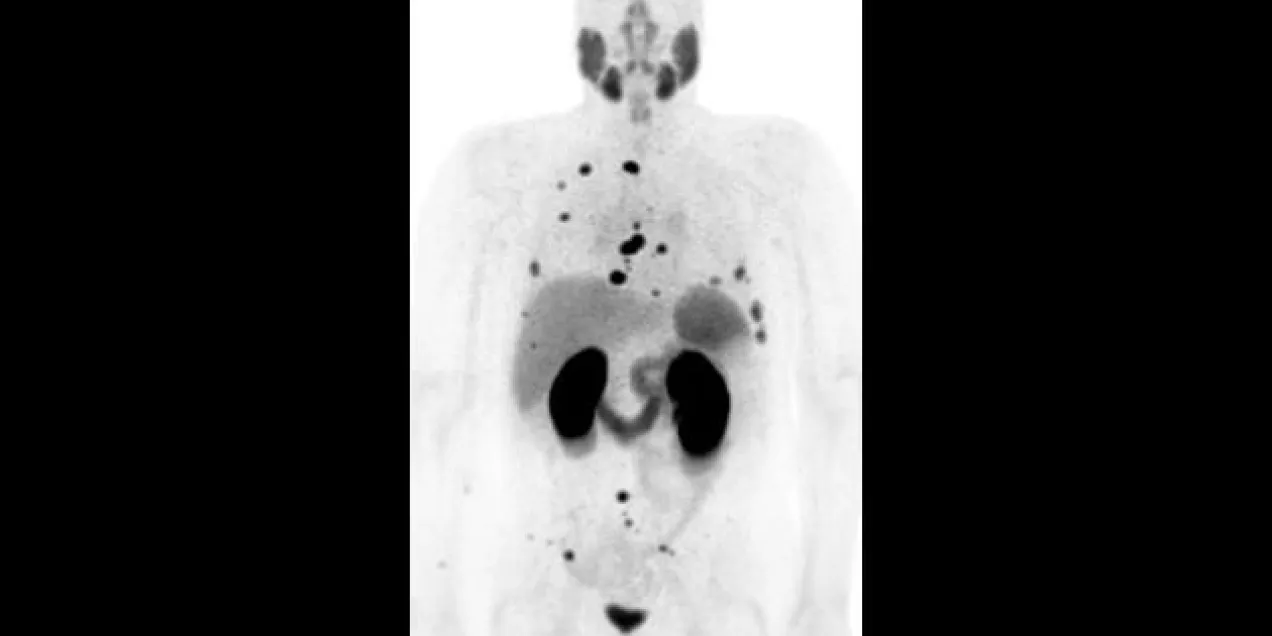

The Chemistry, Probes and Molecular Therapy (CPMT) research group in the Department of Radiology and Biomedical Imaging at UCSF focuses on the development of new molecular imaging tools. This research group will complement our existing research and infrastructure groups to bring targeted therapies to the clinic, for both for the diagnosis and therapy of human disease.